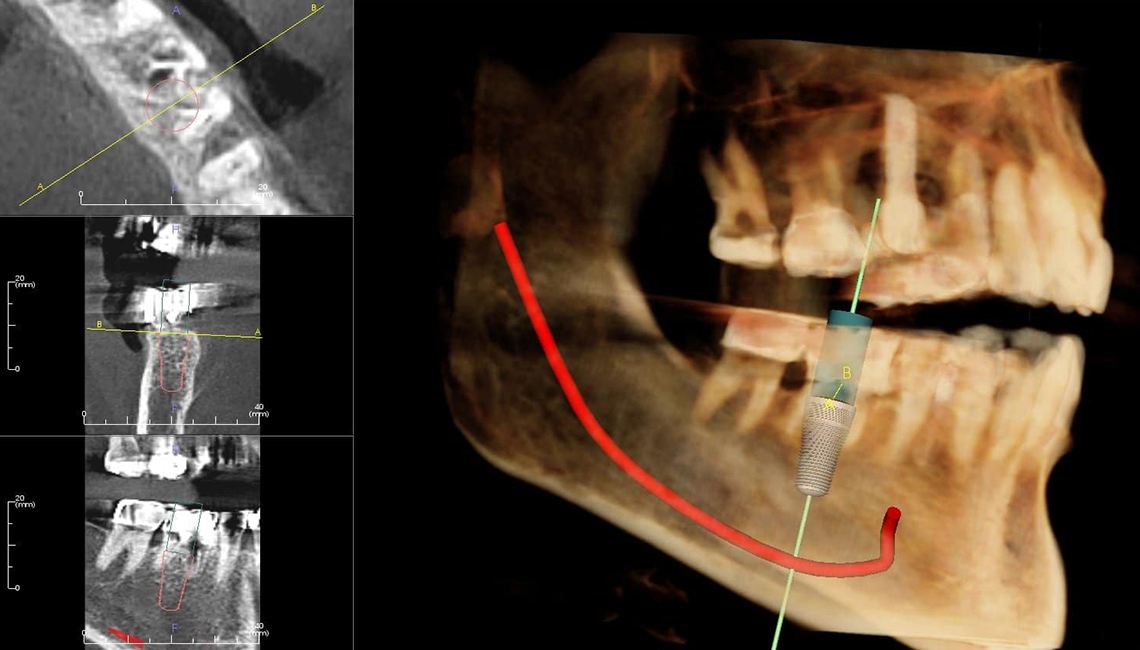

Dental implant surgery is a procedure that replaces tooth roots with metal, screwlike posts and replaces damaged or missing teeth with artificial teeth that look and function much like real ones. Dental implant surgery can offer a welcome alternative to dentures or bridgework that doesn't fit well and can offer an option when a lack of natural teeth roots don't allow building denture or bridgework tooth replacements.

3. Dental implant placement